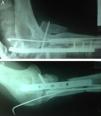

Se realiza una artrodesis de codo con resección del hueso infectado y acortamiento agudo mediante abordaje posterior a través de las cicatrices previas. Se resecan los extremos óseos del húmero distal, el cúbito y el radio proximal hasta obtener hueso sangrante. Se fija en una posición de 80° y pronación de 60° con una placa bloqueada de 3,5 mm (Synthes), se realiza compresión interfragmentaria entre el cúbito y el húmero a través de la placa con un tornillo cortical de 3,5 y se termina la fijación con 4 tornillos bloqueados en húmero, 3 en el cúbito y se realiza un cierre convencional (fig. 2). Los cultivos de los remanentes óseos fueron negativos y el resultado de anatomía patológica descartó recaída tumoral. En la actualidad completa 13 meses de seguimiento clínico después de recibir durante 8 semanas antibiótico oral (trimetoprim-sulfametoxazol y rifampicina) sin evidencia clínica ni paraclínica de infección, sin dolor y con reintegro laboral. La paciente refiere estar satisfecha con el resultado funcional y estético.

A los 3 meses, con los tejidos blandos en condiciones adecuadas, se intervino quirúrgicamente al paciente para reconstrucción del codo. Durante el procedimiento no se encontró superficie articular tributaria de reconstrucción y se decidió realizar artrodesis de codo. Se realizó la artrodesis con placa anatómica de olecranon (Synthes). Se fijó en posición de 110° y pronación de 20° con 5 tornillos corticales proximales y 3 tornillos diafisiarios. Se complementó la fijación con 3 tornillos corticales de 3,5 mm, 2 radiocubitales y 1 radiohumeral. Durante el mismo procedimiento se realizó nueva osteosíntesis del radio proximal por falta de consolidación de la fractura inicial (fig. 4). Se cerró de forma convencional sin problemas de cobertura.